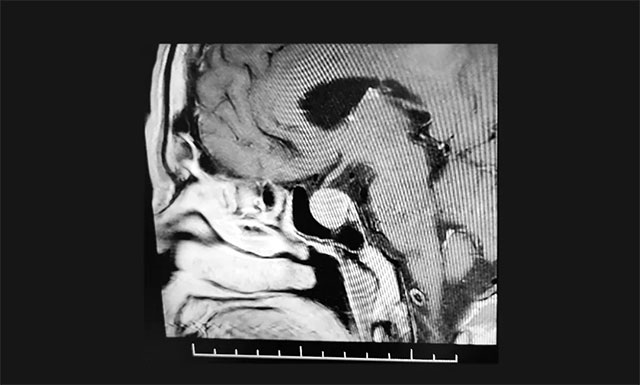

▲ 影像检查显示:垂体大腺瘤,超蝶鞍生长

鞍区MRI增强提示:蝶鞍显著扩大,鞍区(偏左侧)见一实性肿块影,超蝶鞍生长,左侧肿块矢橫高径约1.8*1.5*1.8cm。病变向鞍上生长,突入鞍上池,轻度推移视神经左侧份。鞍底受压变薄下陷,左侧鞍旁海绵窦受侵、外移,血管(颈内A)包绕约1/3以上。

结合病史、影像等,神经外科6B病区潘仁龙主任、李士其教授、吴治群博士会诊后考虑为生长激素垂体腺瘤,正是垂体瘤导致张老伯面容改变、肢端粗大等。手术指征明确,应尽快手术治疗。